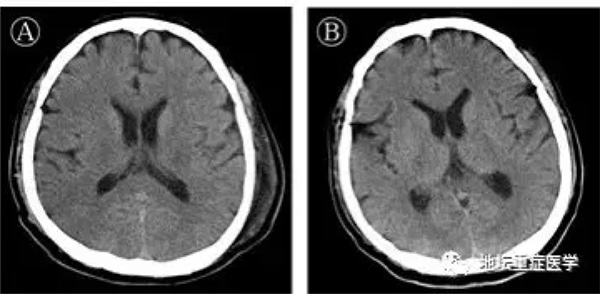

治疗96小时后(起病第14天),患者出现颌面及口角频繁抽搐,伴持续呃逆,医生查体发现颈抵抗阳性,双侧瞳孔等大等圆,对光反射迟钝,四肢肌张力升高,双侧膝反射亢进,双侧巴氏征及踝阵挛阳性,头颅CT颅内未见异常,测脑脊液压力大于330mmH2O,脑脊液外观无色清亮,生化检测无异常。